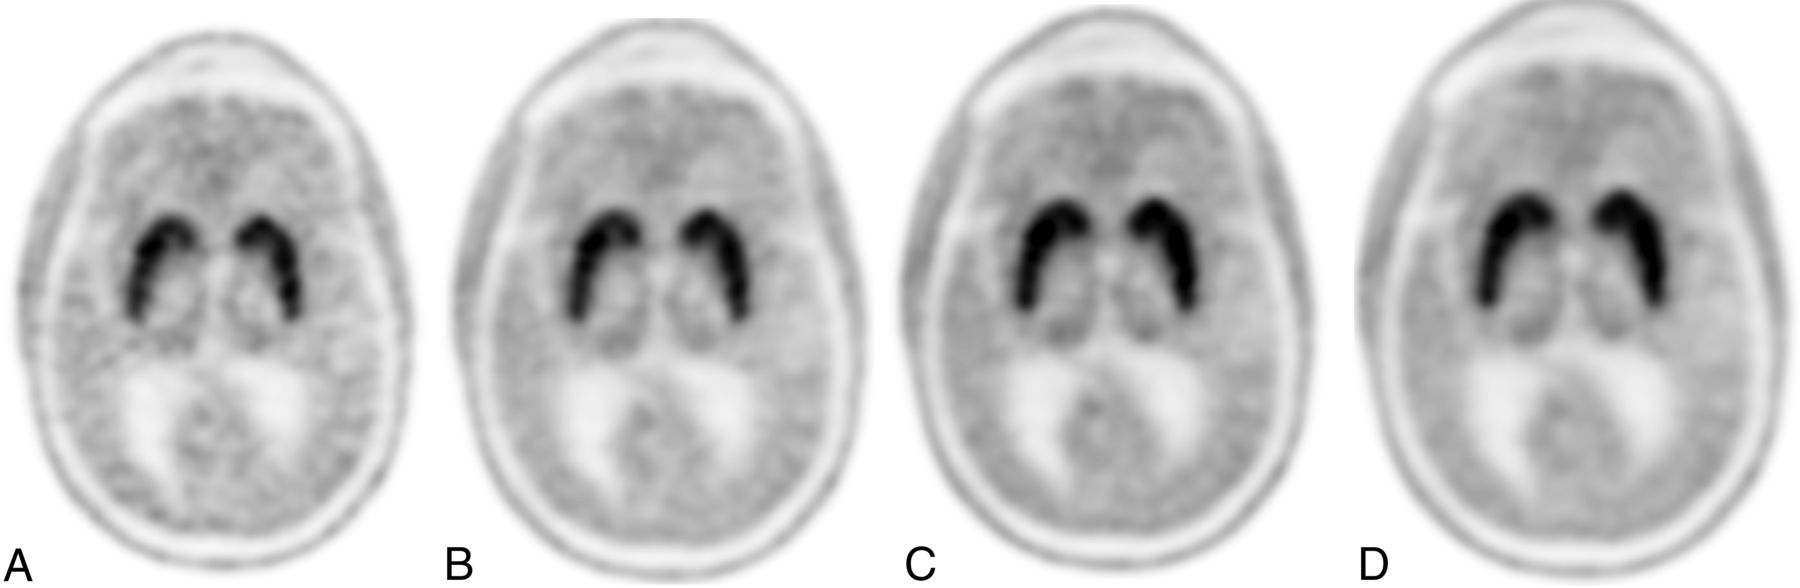

Per the neuroradiologist’s expert read, 10 studies (50%) had abnormal findings as evaluated at the standard 20-minute acquisition time (Fig 1). There was no association between reader confidence and acquisition time (reader 1, ρ = –0.13, P = .250; reader 2, ρ = –0.19, P = .100). However, image-quality ratings were lower among images with shorter acquisition times for both reviewers (reader 1, ρ = 0.23, P = .044; reader 2, ρ = 0.24, P = .036) (Figs 2 and 3).

Normal findings on [18F]-FDOPA AC PET at 5-minute (A), 10-minute (B), 15-minute (C), and 20-minute (D) acquisition times. Note that image-quality ratings were stable following 15 minutes, and between-subject abnormality detection rates were highly consistent between the 2 readers when using 10-, 15-, or 20-minute acquisition times but were inconsistent at 5 minutes.

Abnormal findings on [18F]-FDOPA AC PET at 5-minute (A), 10-minute (B), 15-minute (C), and 20-minute (D) acquisition times. Note that image-quality ratings were stable following 15 minutes, and between-subject abnormality detection rates were highly consistent between the 2 readers when using 10-, 15-, or 20-minute acquisition times but were inconsistent at 5 minutes.

Analysis of interrater reliability (Table 4) revealed that an abnormal finding on an image was rated similarly between readers at 20-, 15-, and 10-minute acquisition times. However, the interrater confidence scores were inconsistent across raters and between the raters and the expert neuroradiologist read at 5 minutes. In contrast, ratings were relatively consistent both in terms of rank order and abnormality agreement when using image-acquisition times of 10–15 minutes. Of interest, the maximal association in confidence scores between raters occurred at 15 minutes (ρ = 0.92), while the maximal κ when comparing raters also occurred at 15 minutes (κ = 0.90).

The goal of [18F]-FDOPA PET visual assessment is to qualitatively analyze uptake in the striatum (putamen and caudate nucleus) by setting the maximum color scale value to the maximal tracer value in the striatum. Moreover, [18F]-FDOPA not only allows qualitative interpretation, but there are established quantitative parameters that can be calculated to objectively quantify the degree of striatal neuronal loss.35⇓⇓-38 Semiquantitative analysis may be performed in the clinical setting, typically by calculating the striato-occipital ratio, which has been shown to correlate with clinical disability ratings.35 Quantitative analysis of dynamic time-activity curves may also be used to determine multiple aspects of [18F]-FDOPA influx constants (Ki maps).36 For example, Dhawan et al38 demonstrated a graphic approach to compare the striatal-to-occipital ratio and influx constant in [18F]-FDOPA PET studies, highlighting a similar accuracy using a short 10-minute scan at 95 minutes post-radiopharmaceutical injection. Similarly, in our study, visual image-quality ratings were stable following 15 minutes, and between-subject abnormality detection rates were highly consistent between 2 readers when using 10-, 15-, or 20-minute acquisition times but were inconsistent at 5 minutes. While acquisition times for PET vary depending on the scanner sensitivity and the administered dose, these results suggest that neuroradiologists may consistently and reliably interpret [18F]-FDOPA PET at acquisition times shorter than the traditionally used 20 minutes.